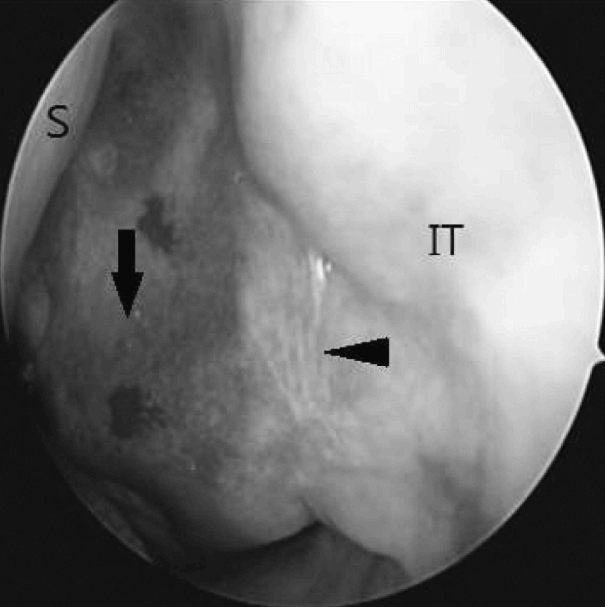

22세 남자가 내원 1년 전부터 심화되는 좌측 코막힘을 주소로 내원하였다. 환자는 1년 전 만성비염으로 개인병원에서 코블레이터를 이용한 하비갑개 성형술을 시행받았으며 수술 이후 좌측 비폐색이 점차 심해져 추가적인 검사 및 치료를 위해 본원을 방문하였다. 과거력상 비염 외 특이질환은 없었고 이전의 안면 및 부비동의 수술이나 외상의 과거력은 없었다. 또한 가족력상에서도 특이사항은 없었으며, 일반 혈액검사 및 일반 화학검사, 혈청검사 및 혈액응고검사상에서도 특이소견은 보이지 않았다. 비강 내시경 소견상 좌측 하비갑개 전방부에 코블레이터 삽입 위치로 보이는 반흔조직이 관찰되었으며 하비갑개 후방부의 비후소견이 관찰되었고 비후조직으로 인해 중비도 및 후비강의 확인은 불가능하였다(Fig. 1). 우측 비강은 심한 비중격의 우측편위 소견을 보였고 종물 등의 특이소견은 보이지 않았으며 비인두에도 특이소견은 관찰되지 않았다. 조영제를 사용한 부비동 전산화단층촬영에서 좌측 상악동을 가득 채운 균일하지 않게 조영 증강된 종괴가 관찰되었으며 종괴는 상악동 내측벽을 밀어내며 팽창하는 양상을 보였다(Fig. 2). 좌측 전사골동부 일부에 부비동염 소견 외 나머지 부비동에 이상소견은 보이지 않았으며 안와저골부의 침범소견도 관찰되지 않았으나 팽창성 종괴에 의해 비중격이 반대편으로 밀리는 소견이 관찰되었다. 혈관종이나 반전형 유두종 및 신경섬유종, 기질화 혈종 등이 의심되어 진단 및 치료를 위해 전신마취 하에 내시경적 접근을 통한 종괴의 절제술을 계획하였다. 수술 시 비강을 통해 내시경 접근법으로 종괴의 변연을 확인하였고 좌측 상악동의 내측 후방 기원의 종괴임을 확인한 뒤 회전절삭기 및 소작기를 사용하여 종괴를 조각 내어 제거하였다. 혈종 발생부위는 상악동 내측 후방부였으며 박리과정에서 접형구개동맥의 분지로 추정되는 동맥의 출혈이 발생하여 흡입기가 연결된 단극성 소작기를 통해 출혈을 조절하였다. 배출된 종괴의 내부는 혈관이 잘 발달되어 있었고 섬유화가 진행되어 단단한 질감이었으며 종괴의 외측부에는 점액성 액체가 포함된 점액낭종이 일부 관찰되었다(Fig. 3). 술 후 병리조직학적 소견에서 종괴는 내부에 풍부한 신생혈관들과 섬유화가 관찰되어 기질화 혈종으로 진단되었다(Fig. 4). 수술 이후 환자의 코막힘 증상은 사라졌으며 6개월간 추적관찰을 한 결과 종괴의 재발소견은 보이지 않았고 부비동 전산화단층촬영상 비중격의 우측 편위도 다소 정상으로 돌아온 것이 확인되었다(Fig. 5).